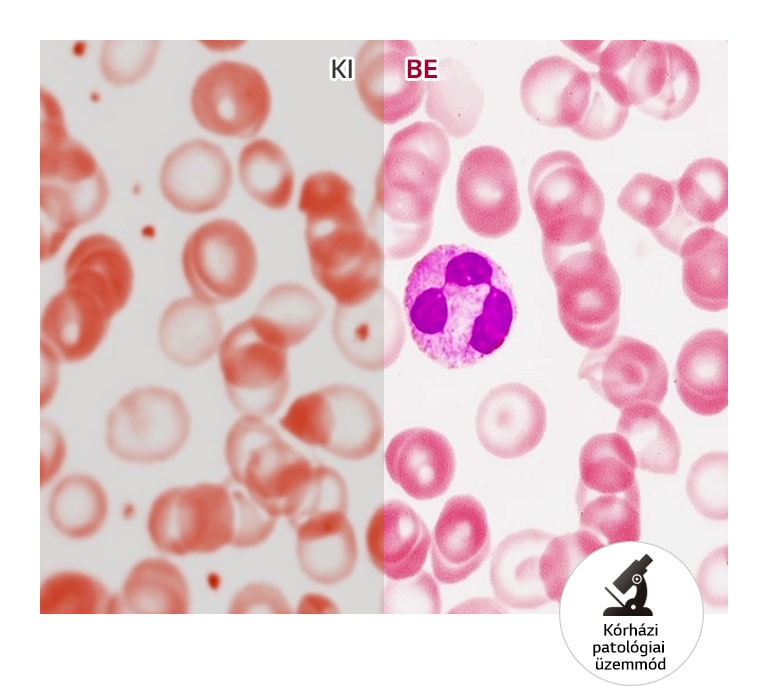

- Kórházi patológiai üzemmód

A beépített automatikus fénykalibrálás folyamatosan stabilizálja a fényerőt és a színmegjelenítést, biztosítva a hosszú távon megbízható képeket. A kórházi patológiai üzemmód optimalizált a finom szín- és fénykülönbségek felismerésére, ideális választás laborok és klinikák számára.

Kórházi patológiai üzemmód – valósághű színmegjelenítés

Az LG 32HL512D kórházi patológiai üzemmódja kifejezetten a színek pontos visszaadására lett kialakítva. Ennek köszönhetően a mikroszkópból érkező képek élénken, mégis torzításmentesen jelennek meg, így a legapróbb részletek is megbízhatóan értelmezhetők.

Klinikai optimalizálás: Kórházi patológiai üzemmód finom szín- és fénykülönbségekhez

Patológiai üzemmód: IGEN